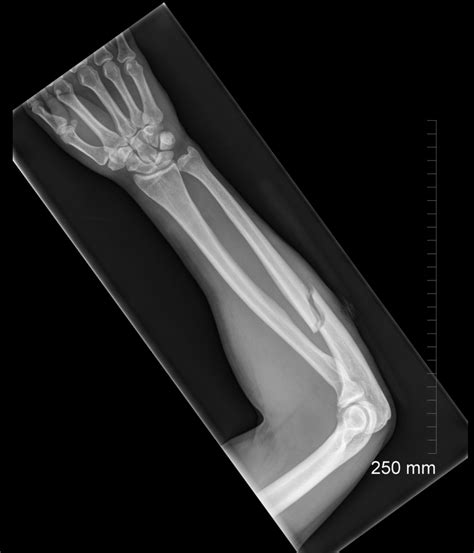

Diagnosing an Ulna Broken Bone

Diagnosing an ulna broken bone involves a thorough medical examination and diagnostic tests. The process typically includes:

• Imaging Tests: X-rays are the primary diagnostic tool for identifying fractures. In some cases, additional imaging tests like CT scans or MRIs may be required for a more detailed view.

Imaging tests are crucial for determining the type and severity of the fracture, which will guide the treatment plan.